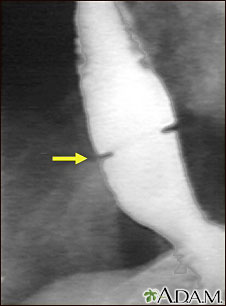

A solution containing a dye (barium), which is visible on x-rays, has been swallowed (upper GI series) and x-rays have been taken of the esophagus. There is a narrowing near the stomach (indicated by the arrow). This non-cancerous ring of tissue (Shatzki ring) may cause swallowing problems (dysphagia) and can be treated with dilation of the stricture.